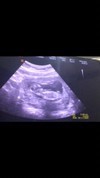

รูปอันตร้าซาวน์ของลูก

ท้องสองยังตื่นเต้นอยู่เลยค่ะ 10w1d แม่ๆบ้านไหนคลอดเดือนพฤศจิกายนบ้างคะ. ขอดูรูปอันตร้าซาวน์แม่ๆหน่อยค่ะ

12w5d